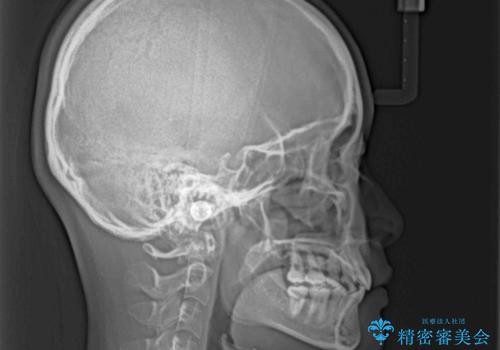

深い咬み合わせの改善に時間がかかりましたが、下顎前歯がしっかりと見えるまでに整えることができ、口元の突出感も大幅に改善することができました。